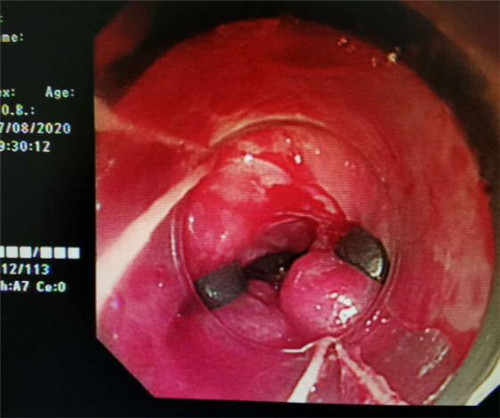

手术中,在镜下发现数条食管静脉曲张延伸至胃底,胃腔内有大量新鲜红色血液及血凝块,寻找到出血部位时仍在向外渗血,血压持续下降,患者时刻有生命危险。曹鹏副主任当机立断对曲张静脉破口处进行组织粘合剂及硬化剂注射,并对曲张静脉进行套扎治疗,在麻醉师陈琦的保驾护航下,整个过程不到半个小时,为患者成功止血,患者转危为安。